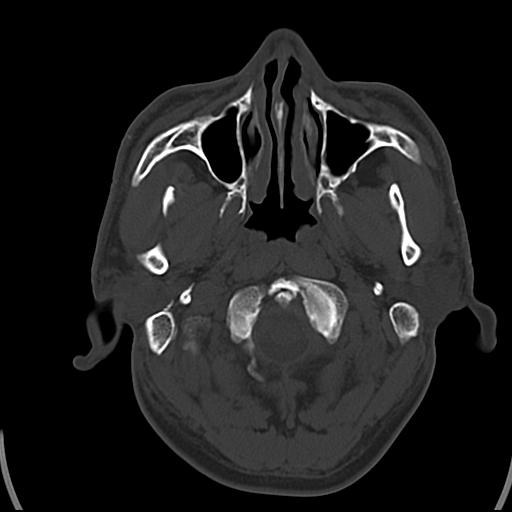

头皮下高密度结节影???临床上在老年男性比较常见。大家看看是什么?成因是? 本例患者,男性,51岁。外伤来诊。无染发史及发根植入史。

皮下钙化点

没见过,可能为毛囊钙化。

考虑钙化。